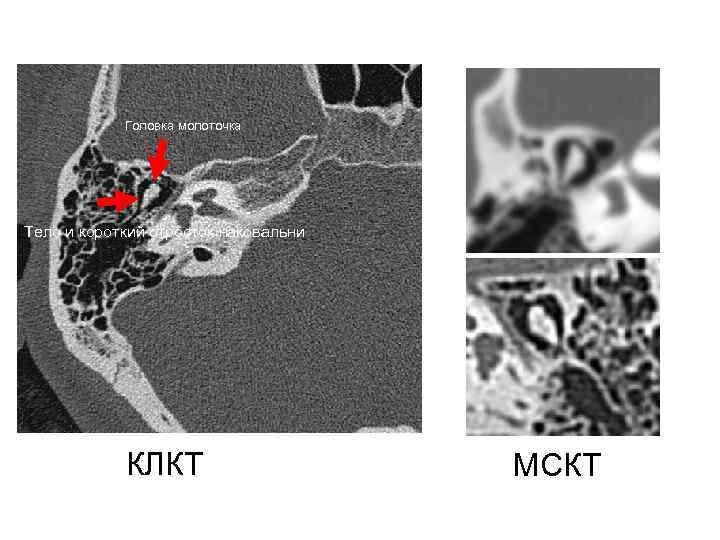

Головка молоточка Тело и короткий отросток наковальни КЛКТ МСКТ Головка молоточка Тело и короткий отросток наковальни КЛКТ МСКТ